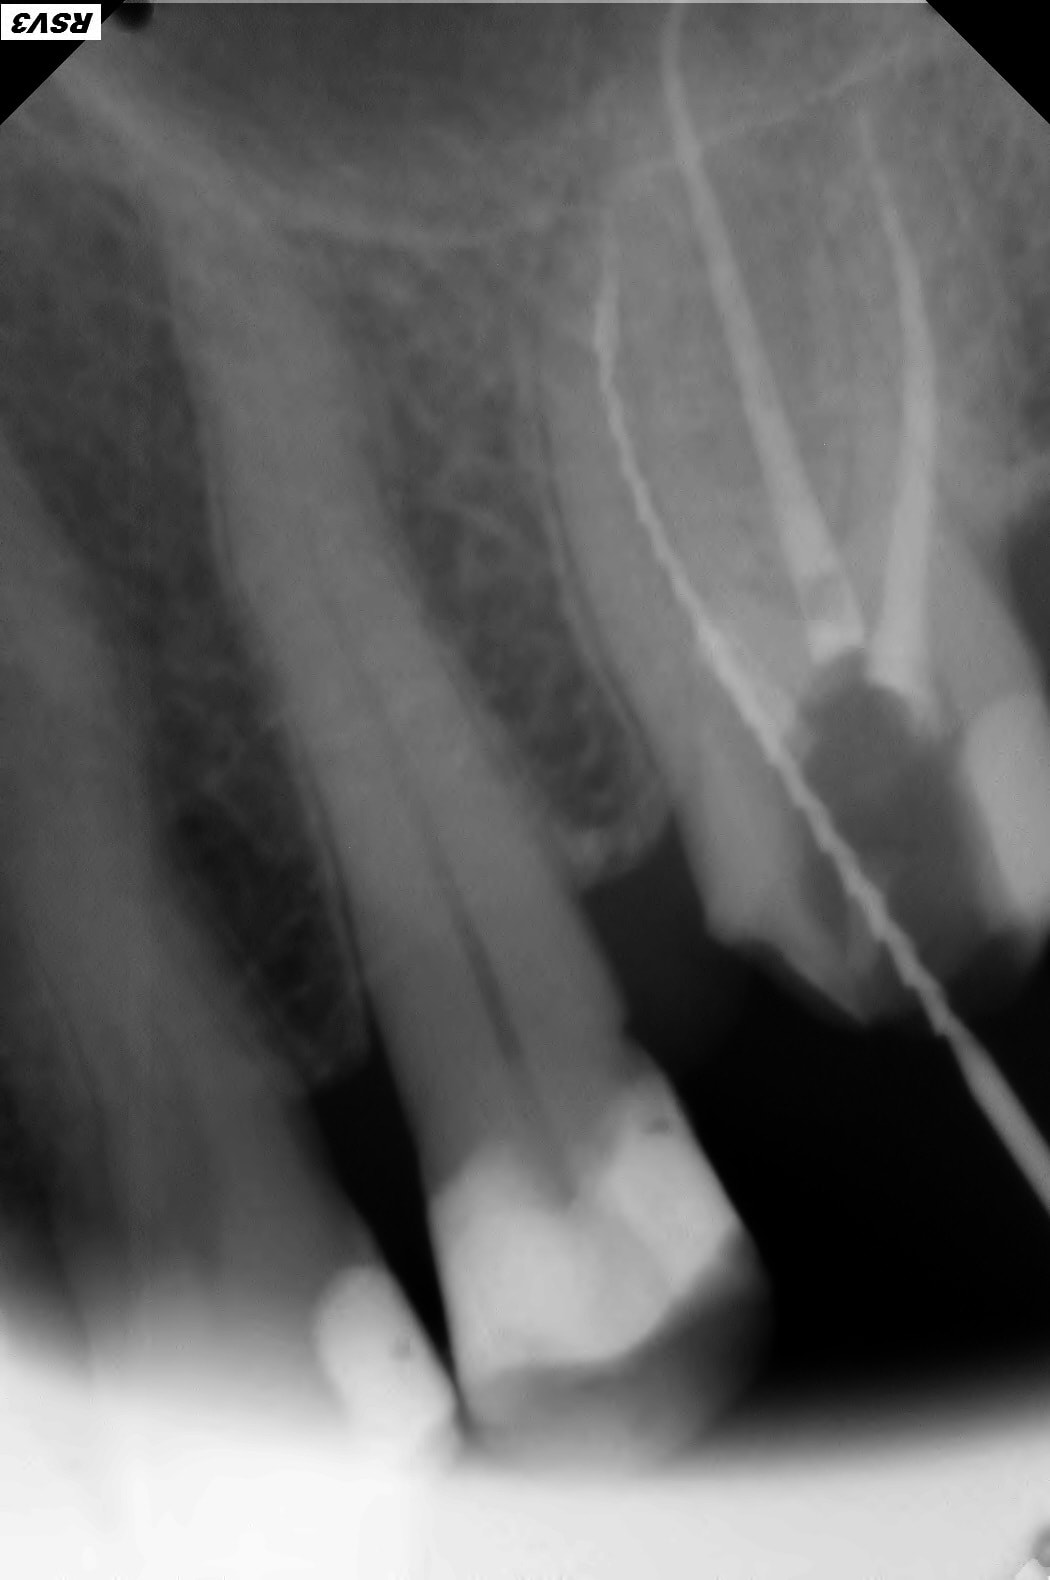

J'ai fait un conebeam de la 26.

L'obturation des racines est correcte, il y a juste une petite image apicale au niveau de la racine palatine avec un léger dépassement de pâte.

Pas de coupes horizontales ?

Le MV2 non obturé ici peut parfois, selon sa configuration, causer des douleurs variées.

Je peux me tromper, les coupes ne sont pas idéales pour conclure ☝️

Pour répondre à Dentarue: je viens de faire des coupes horizontale et centrées sur la racine vestibulaire en tournant autour d'un potentiel MV2. La gutta et le ciment font un joli artefact radio donc ce n'est pas concluant.

On le voit très bien sur ta 3d.

Aucune gloire, on ne voit que ça.

Chercher une deuxième entrée en vestibulaire quand on voit sur cette coupe et sur la coupe horizontale que c’est le palatin qui n’est pas obturé, … les mots me manquent.

Il cherche en vestibulaire de MV mais c’est en palatin de MV qu’il fallait chercher, cela me semblait aller sans dire ☝️

Tout est sur la 3d.

Le MV2 n’est pas très proche de la furcation mais plutôt plus mésial que le MV1. Il est très visible à la radio et ne doit pas être bien compliqué à traiter, mais pour ça il faut s’en donner les moyens et ça commence par la digue.

Tu nous dis qu’il n’y a pas de MV2 et tu nous montres des coupes où il saute aux yeux puis tu vois la patiente entre deux pour désobturer MV1 sans digue… et laisser MV2 non traité…

Il est plus mésial.